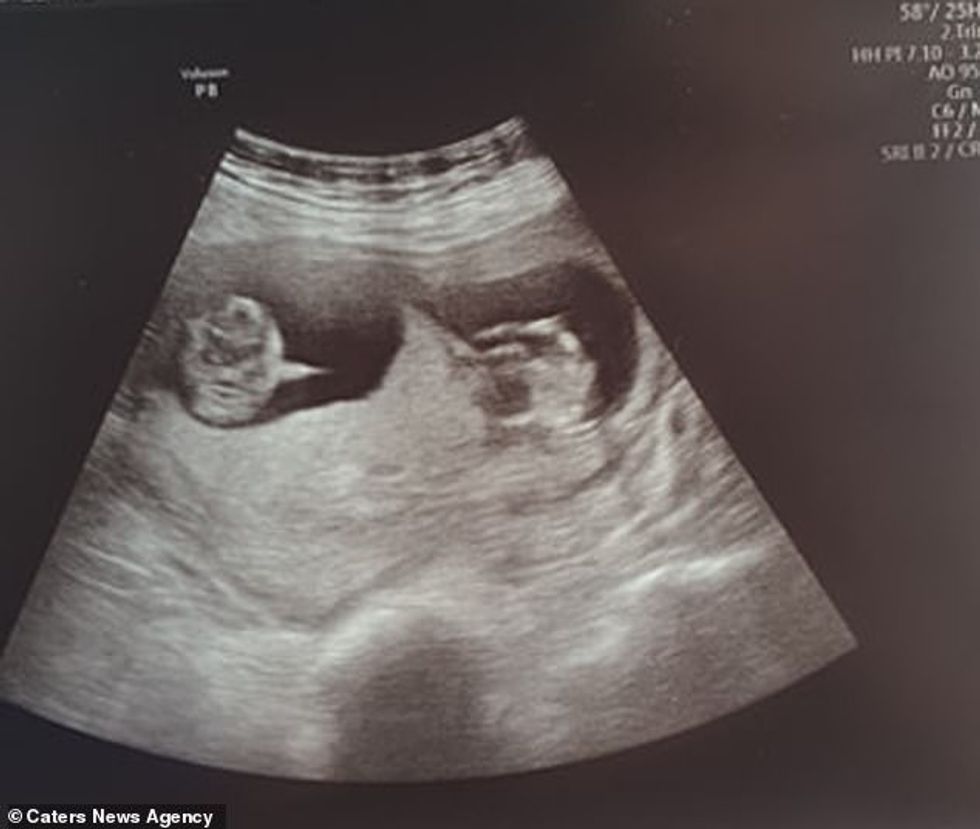

Por, zonja martin ishte në javën e nëntë të shtatzënisë por ajo nuk e priste se do të kishte dy binjakë.